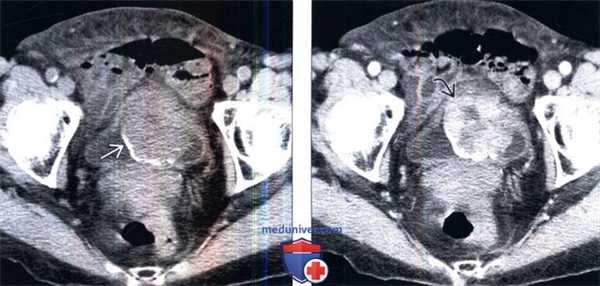

(Слева) КТ без контрастирования, аксиальный срез: у женщины 76 лет с макрогематурией и болью в малом тазу определяется крупное образование мочевого пузыря с частично кальцинированной поверхностью.

(Справа) КТ с контрастированием, аксиальный срез: у этого же пациента определяется прерывистое контрастирование объемною образования. Околопузырная жировая клетчатка, прилегающая к образованию, не имеет четких границ, что позволяет предположить пристеночное распространение этого процесса. (Слева) КТ с контрастированием, более каудальный аксиальный срез: у этого же пациента определяется прерывистое контрастирование объемного образования с зоной центрального некроза.

(Справа) КТ с контрастированием в отсроченную фазу: у этого же пациента определяется полипоидное образование в виде дефекта наполнения в констрастируемой моче. Отмечается наличие широкого основания, которым образование прикрепляется к стенке мочевого пузыря. При хирургическом вмешательстве эту опухоль было очень трудно удалить. По данным исследования замороженного среза была предположена саркома, однако окончательным диагнозом стала воспалительная псевдоопухоль мочевою пузыря.

(Справа) КТ с контрастированием, аксиальный срез: у этого же пациента определяется прерывистое контрастирование объемною образования. Околопузырная жировая клетчатка, прилегающая к образованию, не имеет четких границ, что позволяет предположить пристеночное распространение этого процесса.

(Слева) КТ с контрастированием, более каудальный аксиальный срез: у этого же пациента определяется прерывистое контрастирование объемного образования с зоной центрального некроза.